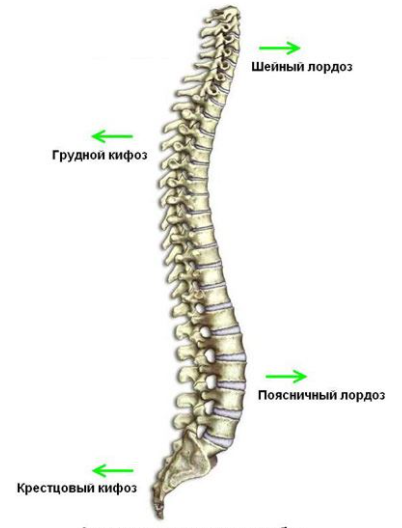

- 布骨医学科普:颈椎的生理曲度变直,如何康复? 布骨康复医疗中心 ,2021-05-13

- 人的颈椎由7节椎骨组成,每节椎骨之间由前方的椎间盘和后方的小关节相连,另外椎骨周围特别是颈后部有很多的肌肉把它们连接在一起。正常情况下,我们的颈椎骨连在一起会形成一条向前突出的曲线,就像是一张向前拉开的弓,而颈后部的肌肉就像是弓弦。形成这样的曲线,或者称为“生理曲度”,是有一定的道理的那为什么会出现.....